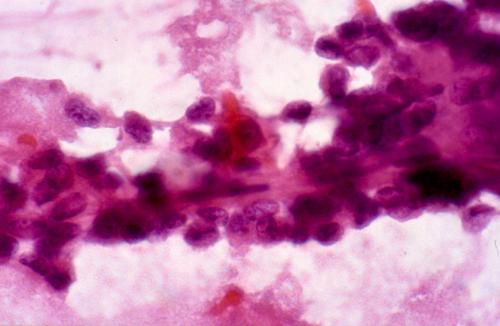

Figure 3. Tumor cells from a solid and cystic papillary tumor of the pancreas. Note the fibrovascular core among the tumor cells. H.E. 1000x.